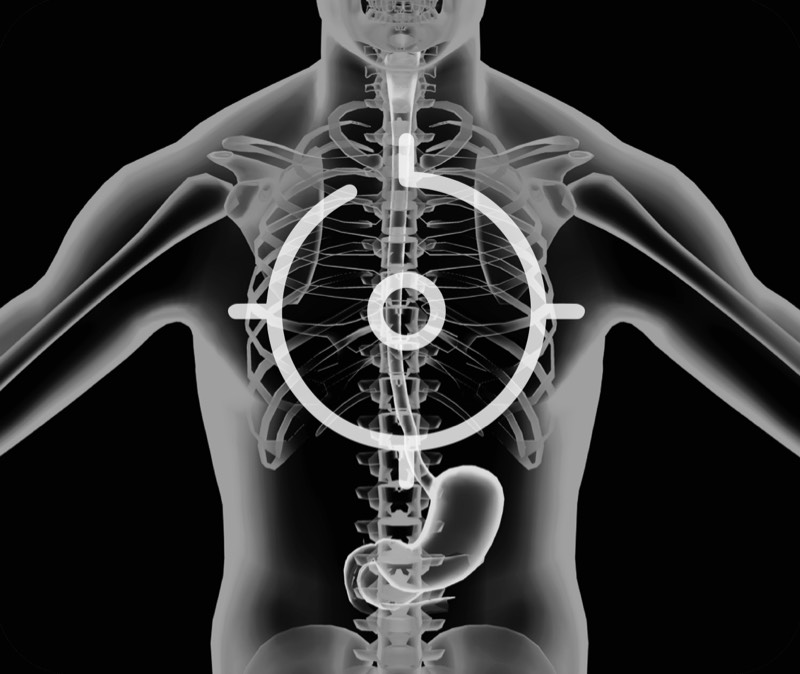

食管内间质瘤清晰显像

360°电子环形扫查与高清内镜影像相结合,提供了良好的插入性能和高清的内镜图像

卓越的宽频设计,满足医生探查不同深度的组织和器官